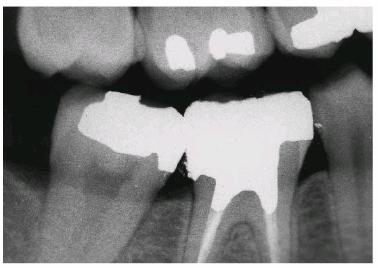

For molars, if there is little remaining tooth structure or the pulp chamber is

shallow, then a post should be used to provide retention for the core (Figur 323s1823d e 18-13A). Usually, only one post is needed.

A prefabricated post should be cemented into the largest canal. In mandibular

molars, this will typically be the distal canal. No attempt should be made to

place a post in the mesial canal of a mandibular molar as the distal wall of

the mesial root is thin and easily perforated. For maxillary molars, a single

post in the lingual canal is adequate. Because the direction of the post is

divergent from the pulp chamber, it creates excellent retention for the core (Figur 323s1823d es 18-13B 18-13C 18-13D 18-13E, and 18-13F

Figur 323s1823d e 18-13A: Prefabricated post with core.

Figur 323s1823d e 18-13B: Tooth #3 after successful root canal treatment.

Figur 323s1823d e 18-13C: Inadequate pulp chamber wall height and lack of remaining tooth structure evident after removal of previous restorative materials. Additional retention with prefabricated post is indicated.

Figur 323s1823d e 18-13D: Completed core build-up on tooth #3.

Figur 323s1823d e 18-13E: Completed crown preparation on tooth #3. Note that the preparation margin extends apical to the core-tooth interface.

Figur 323s1823d e 18-13F: Composite resin may also be used as core material.